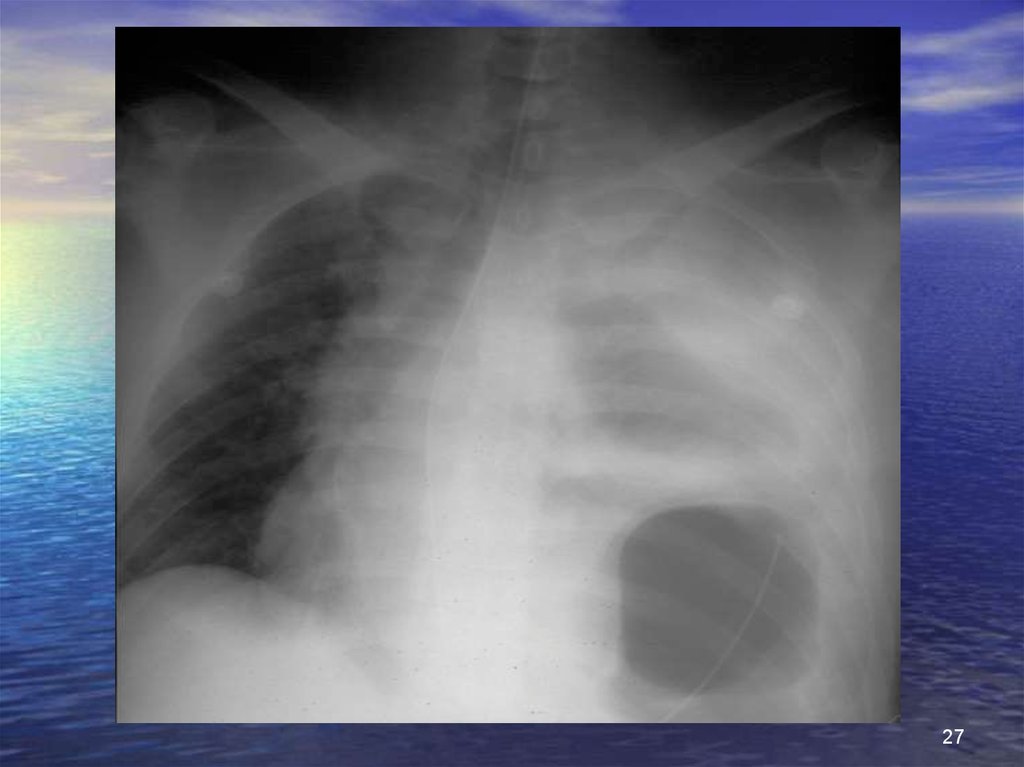

27.

27